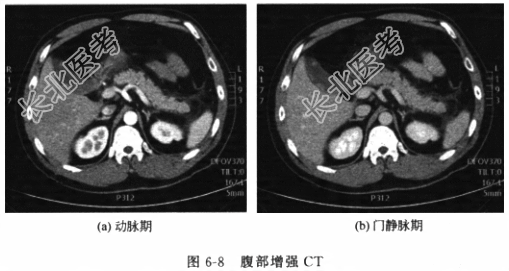

- [材料题] 患者女性,79岁,因“反复右上腹不适1个月余”入院。患者于1个月前始反复出现右上腹闷胀不适,偶伴右肩部酸胀,恶心、纳差,当时未予重视,自行口服“胆舒胶囊”,症状略有好转,但不久又出现上述不适,遂就诊于我院普外科门诊,查超声提示为“胆囊占位”,为进一步诊治住入我科。病程中无发热、黄疸、胸闷、咳嗽、腹痛、腹胀、血尿和尿频等不适。发病以来,一般情况尚可,大小便无异常。否认有手术史。体格检查体温(T)36.8℃,呼吸(R)20次/分,脉搏(P)68次/分,血压(BP)105/70mmHg。神志清楚,皮肤黏膜光滑,巩膜无黄染。腹部平坦,未见胃肠型或蠕动波,无压痛、反跳痛和肌紧张,全腹未扪及包块,叩诊呈鼓音,肠鸣音2~5次/分。直肠指检未及异常占位,退出时指套无染血。辅助检查血常规示白细胞8.9×10⁹/L,中性粒细胞88%,其他实验室检验结果包括肝肾功能、电解质、血气分析和肿瘤标志物结果未见明显异常。腹部肝胆胰脾肾超声(图6-7)提示胆囊占位,深度达肌层,尚未突破浆膜层。腹部CT(图6-8)提示胆囊底部新生物向胆囊腔内突起,直径约1cm,增强有强。